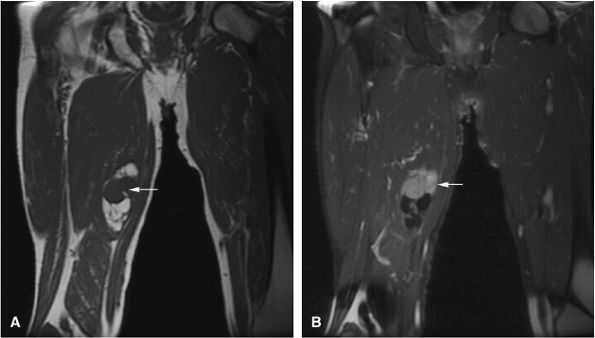

FIGURE 14-6 ● Coronal T1-weighted image (A) and coronal STIR image (B) demonstrate red marrow heterogeneity (arrow) in the femoral diaphysis and metaphysis without extension across the physeal scar.

Red-to-yellow marrow conversion in middle-aged women (marrow inhomogeneity is especially common in obese women with a history of smoking) is seen in metaphyseal or diaphyseal areas of low signal intensity (i.e., red marrow) without extension into the epiphysis (Fig. 14-6). These lesions become isointense with

adjacent marrow on heavily T2-weighted images and demonstrate increased signal intensity on STIR images. Inhomogeneity of metaphyseal red and yellow marrow may also be observed in the immature skeleton.